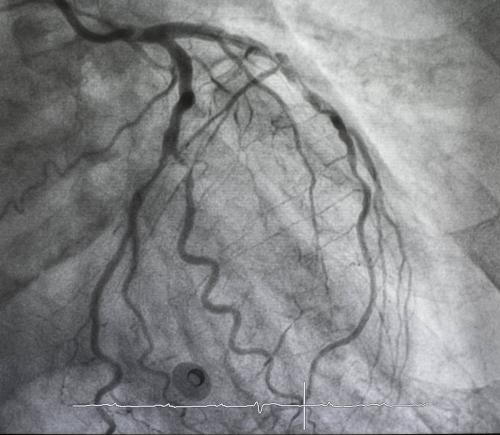

Left coronary angiography showing coronary arteries

A heart angiogram is an imaging procedure that allows direct visualization of the coronary arteries. These arteries supply oxygen-rich blood to the heart muscle. During the procedure, contrast dye enters the bloodstream and highlights the arteries on specialized imaging. This process shows whether arteries remain open or contain narrowing or blockages that restrict blood flow.